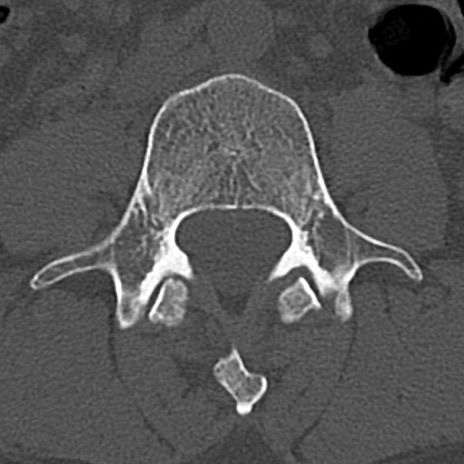

腰椎CT

横断像と矢状断像